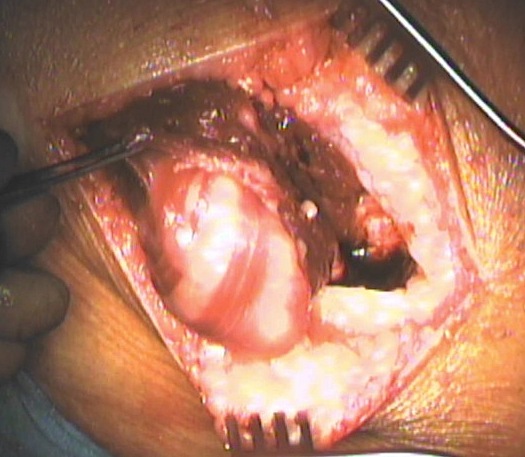

Intra-muscular lipoma

4. Intramuscular